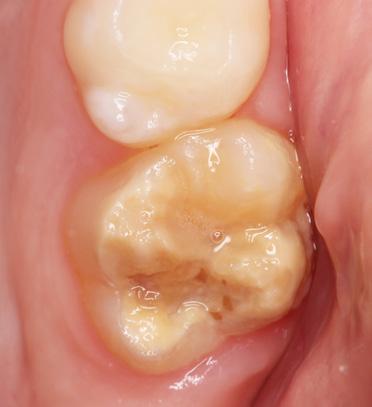

Für die Diagnose einer MIH ist der klini sche Befund entscheidend. Kriterien zur Erfassung der hypomineralisierten Zähne liegen von der EAPD vor [14], die wie folgt festgelegt sind: klar umschriebene Opazi täten (Abb. 1, 2), posteruptive Schmelzab brüche (Abb. 1), atypische Restaurationen (Abb. 3) und atypische Extraktionen. Diffe rentialdiagnostisch müssen u. a. folgende Krankheitsbilder in Betracht gezogen wer den: Fluorosen, erbliche Strukturanoma lien (Amelogenesis imperfecta) und exogen bedingte Defekte (Trauma, Turnerzahn, Karies).

Abb. 1: MIH an den Zähnen 16 und 26. Zahn 16 weist bereits einen posteruptiven Schmelzeinbruch im distalen Bereich auf, Zahn 26 zeigt abgegrenzte Opazitäten. Abb. 2: Patientin aus Abb. 1. Die beiden mittleren oberen Inzisiven zeigen jeweils eine umschriebene Opazität.

Abb. 3: Atypische Restauration bei einem von einer MIH betroffenen oberen Molar. Im Randbereich der Füllung sind Opazitäten erkennbar.

Pour le diagnostic d’une MIH, le résultat clinique est décisif. Des critères de dé tection des dents hypominéralisées sont disponibles auprès de l’EAPD [14] et sont définis comme suit: opacités claire ment circonscrites (fig. 1, 2), cassures postéro-supérieures de l’émail (fig. 1), restaurations atypiques (fig. 3) et extrac tions atypiques. Le diagnostic différen tiel doit prendre en compte, entre autres, les pathologies suivantes: fluoroses, anomalies structurelles héréditaires (amélogénèse imparfaite) et défauts d’origine exogène (traumatisme, dent de Turner, carie).

Fig. 1: MIH sur les dents 16 et 26. La dent 16 présente déjà un effondrement postéroéruptif de l’émail dans la zone distale, la dent 26 présente des opacités délimitées.

Fig. 3: Restauration atypique sur une molaire supérieure affectée par une MIH. Des opacités sont visibles dans la zone marginale de l’obturation.